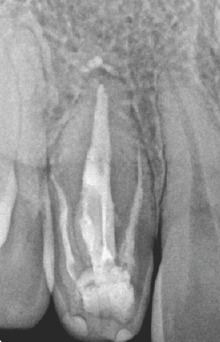

Clinically, dens invaginatus appears in the tooth crown at the site of an anatomical lingual pit susceptible to caries.(3) Radiographically, it shows a radiopaque invagination, equal in density to enamel, extending from the cingulum into the root canal.(1) The defects may vary in size and shape from a loop like, pear-shaped or slightly radiolucent structure to a severe form resembling a “tooth within a tooth”.(4) It can be identified easily because infolding of the enamel lining is more radiopaque than the surrounding tooth structure.(1)

Case Description: The 17 y.o. Asian, female patient presented to our office with a complaint of “my dentist told me I don’t have a root, that it was fused when I was born. I had pain one year ago and then again two months ago. My face was swollen and the dentist put me on antibiotics.” She was referred for teeth #6 & #7. Tooth #7 did not respond to cold, but all other teeth tested normally. Both #7 & #10 presented with dens invaginations. The lamina dura and periodontal ligament(PDL) were not intact around #7. The lamina dura was intact around #10 and the PDL was widened. A diffuse radiolucency was noted around the apices of #7, which also appeared to encroach upon #6 and #8. A widened PDL was noted around #6. Tooth #7 was diagnosed as: necrotic pulp and asymptomatic apical periodontitis. Tooth #10 was diagnosed as: normal pulp, normal periodontium.

Figure 1: Periapical radiograph showing a maxillary right lateral incisor with four dens invaginatus Figure 2: Periapical radiograph showing a maxillary left lateral incisor with one dens invaginatus